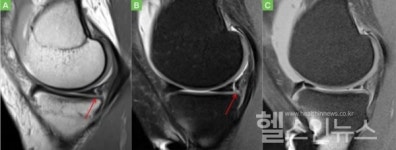

![[이상학 교수의 건강칼럼] 전방십자인대파열 환자, 10명 중 2~3명은 램프병변 함께 발생](https://search.pstatic.net/common/?type=b150&src=http://imgnews.naver.net/image/5817/2020/11/02/0000001549_003_20201102131439351.jpg)